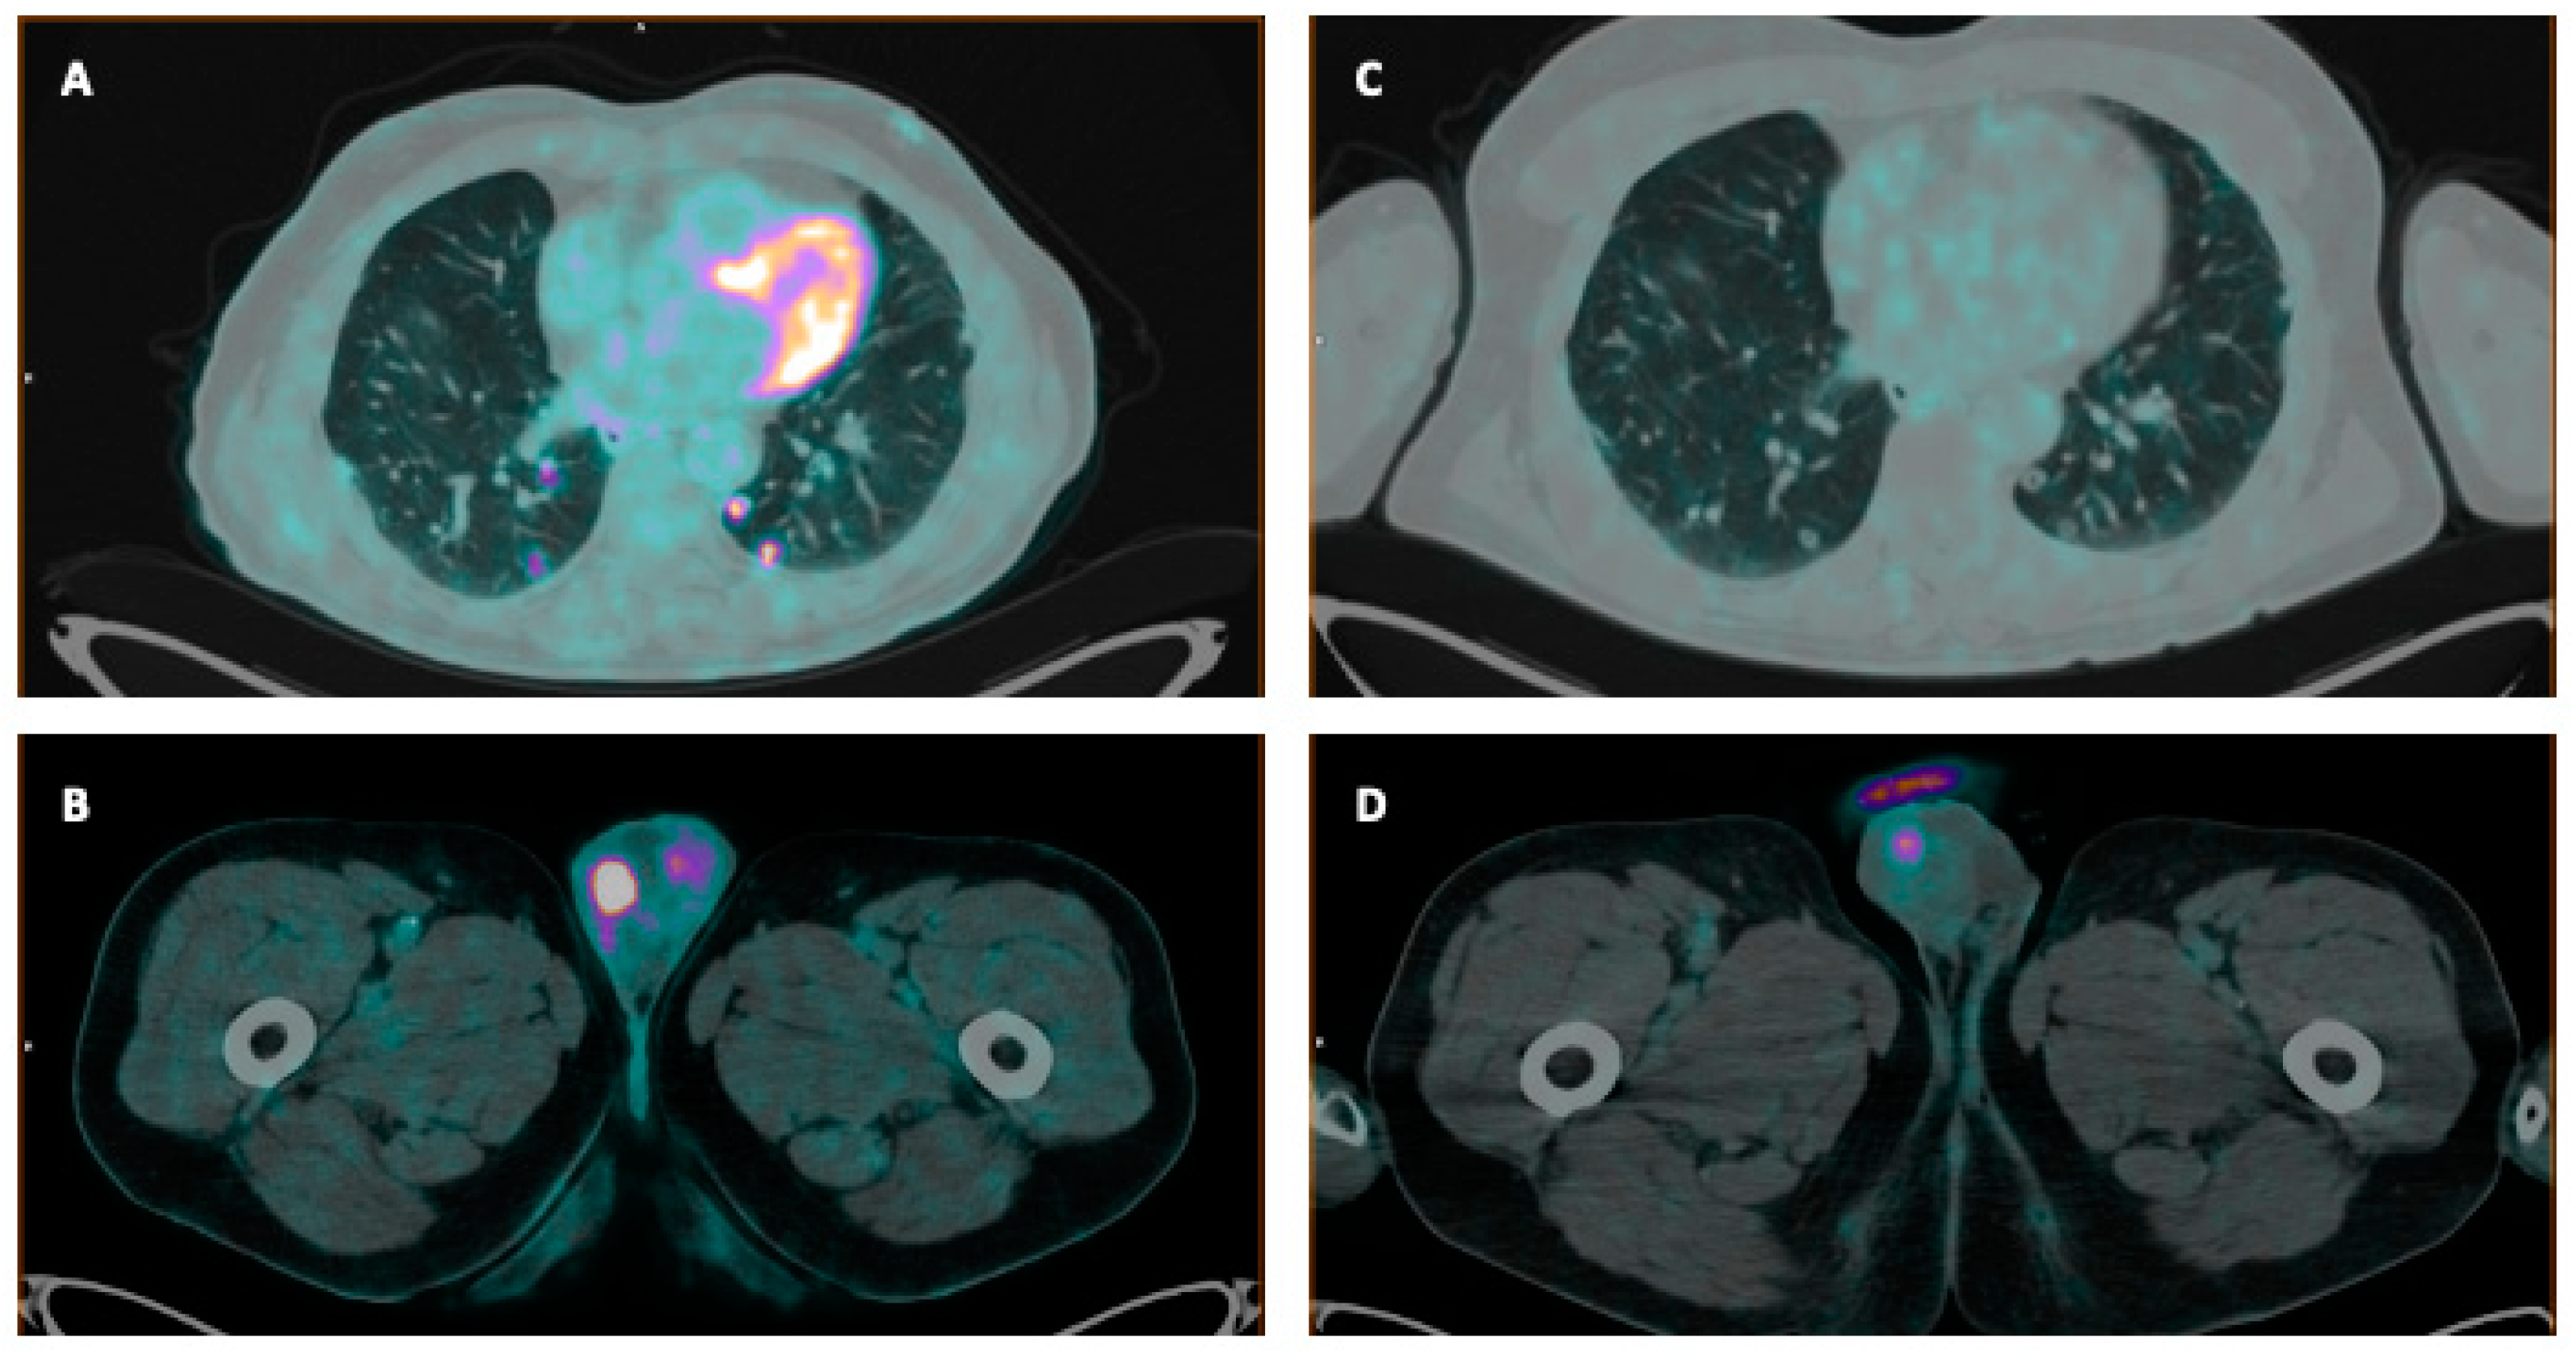

- Perez, P.M.; Hope, T.A.; Behr, S.C.; van Zante, A.; Small, E.J.; Flavell, R.R. Intertumoral Heterogeneity of 18F-FDG and 68Ga-PSMA Uptake in Prostate Cancer Pulmonary Metastases. Clin. Nucl. Med. 2019, 44, e28–e32. [Google Scholar] [CrossRef]